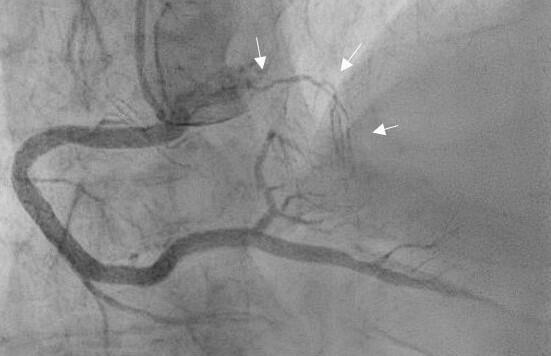

Test Your Knowledge: Identifying Unusual Coronary Anatomy